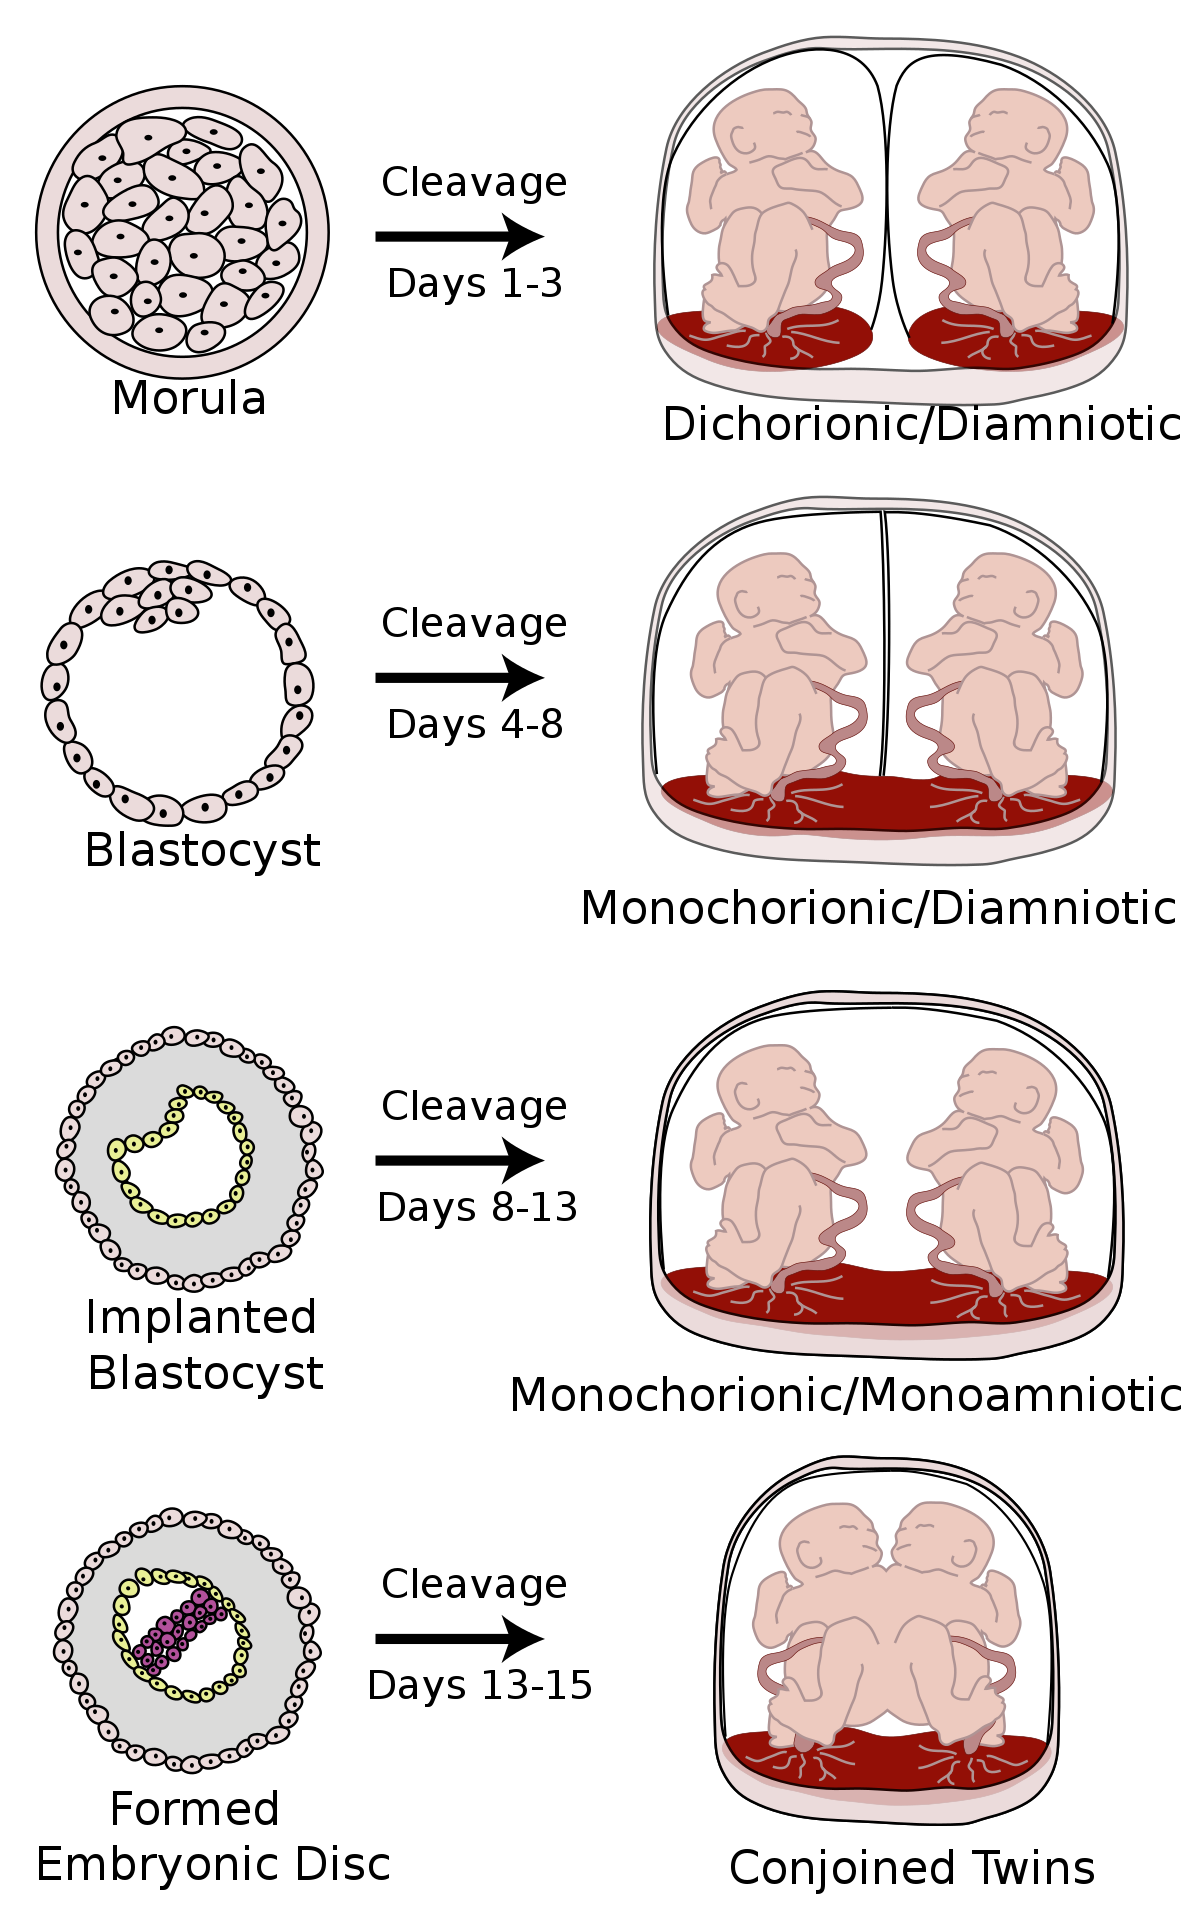

Pada awal Kehamilan kembar, pemeriksaan ultrasonografi (USG) kehamilan dilakukan untuk melihat apakah setiap janin memiliki korion dan kantung ketuban sendiri.

Terdapat tiga jenis kembar:

- Dikorionik diamniotik, yaitu kembar yang memiliki korion dan kantung ketuban sendiri. Mereka biasanya tidak berbagi ari-ari dan dapat merupakan kembar fraternal atau identik

- Monokorionik-diamniotik, yaitu kembar yang berbagi korion namun memiliki kantung ketuban yang terpisah. Mereka berbagi plasenta dan merupakan kembar identik

- Monokorionik-monoamniotik, yaitu kembar yang berbagi satu korion dan satu kantung ketuban. Mereka berbagi plasenta dan merupakan kembar identik